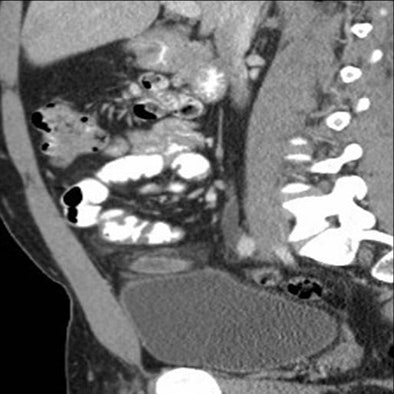

![]() |

| Above, small-bowel obstruction diagnosed with both oral and IV contrast. Below, another patient with small-bowel obstruction diagnosed with IV contrast alone. |